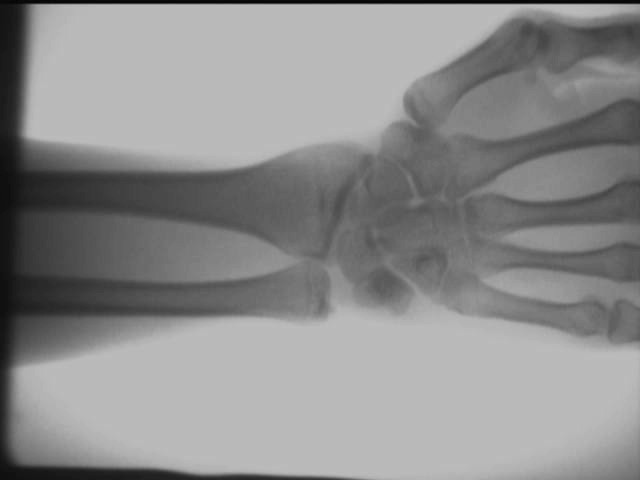

Qo'l to'pig'i qo'shma ta'siri

Yuqoridagi sinov natijalari AS-C200 yordamida joyida olinadiportativ rentgen apparati